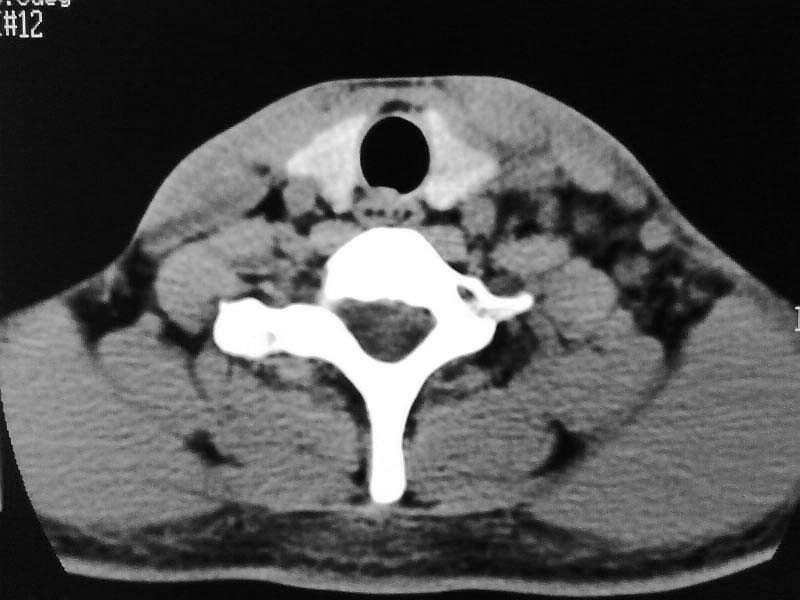

以下是引用余辉在2009-5-3 11:36:00的发言:[br]左侧胸锁乳突肌下方不规则肿物影,边界不清,内部密度不均,左侧颈外侧区脂肪增多,多发淋巴结肿大,考虑淋巴或神经来源肿瘤可能性大,不除外淋巴结炎,肌源性肿瘤及增生性肌炎等,活检